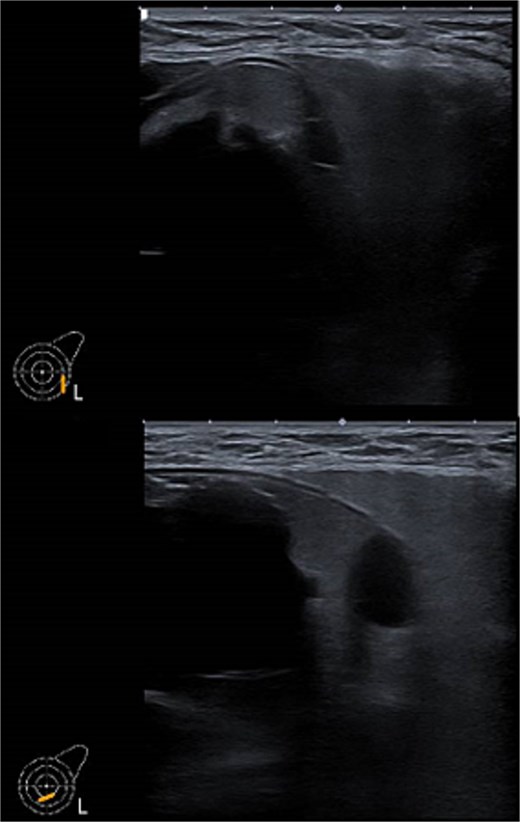

Ultrasound of left breast and axilla: Revealed rupture of the left implant with intracapsular and extracapsular leakage, along with echogenic peri-implant fluid. Enlarged axillary lymph nodes were visualized (Figs 1 and 2).

Ultrasound of the left axilla showed the typical appearance of the lymph node siliconoma.